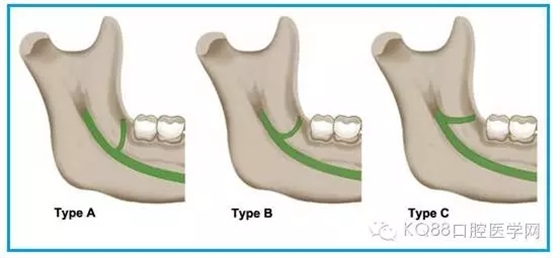

圖一 磨牙后區(qū)的形態(tài)學(xué)分類(綠色標示):

A.水滴形;

B.細長型;

C.三角形。